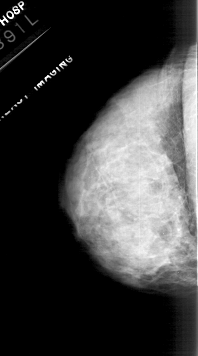

RIGHT_CC LINES 4741 PIXELS_PER_LINE 2611 BITS_PER_PIXEL 12 RESOLUTION 43.5 OVERLAY

FILE: A_1113_1.RIGHT_CC.OVERLAY

TOTAL_ABNORMALITIES 1

ABNORMALITY 1

LESION_TYPE CALCIFICATION TYPE PLEOMORPHIC DISTRIBUTION CLUSTERED

ASSESSMENT 4

SUBTLETY 3

PATHOLOGY MALIGNANT

TOTAL_OUTLINES 1

BOUNDARY